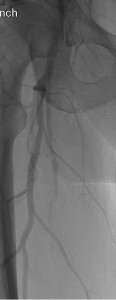

A 57-year-old diabetic man with a history of left femoral-popliteal bypass grafting presents with progressive right leg claudication. His symptoms began 5 years ago and were characterized by exertional right calf pain and bluish discoloration of the first and third digits. As he had initially presented years prior with similar symptoms in the left leg, there was concern for atheroembolism resulting in acute limb ischemia. Urgent angiography at that time revealed an occlusion of the right superficial femoral artery with collaterals and reconstitution at the adductor canal above the knee.

There was a patent popliteal artery and three-vessel runoff to the foot. The patient was started on aspirin, clopidogrel and cilostazol and was initially very pleased with his level of function on medical therapy. However, he eventually developed progressive intermittent claudication in the right leg and the decision was made to pursue endovascular revascularization.

Back to the Patient

Noting both significant lesion length (~18 cm) and ostial location without calcification in our patient, we anticipated that a re-entry device might be successful (if necessary) and proceeded with antegrade probing of the CTO using an 0.035-inch angled Glidewire (Terumo, Somerset, NJ) and Seeker catheter (Bard, Tempe, AZ). As the wire could not be tracked in a straight line, we formed a loop and gently dissected subintimally to just above the knee, at which point we were able to maneuver into the reconstituted SFA.